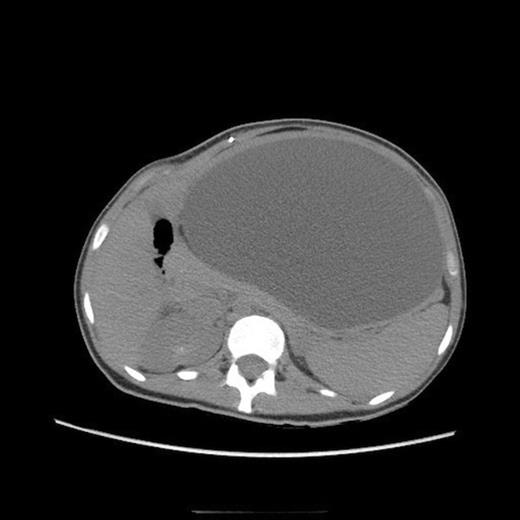

Post-operative abdominal CT demonstrating complete resolution of the fluid compartment

The patient underwent laparoscopic cyst drainage with removal of the cyst wall. A total of 12.7L of fluid was drained. Culture results and routine labs were all negative. A post-operative CT demonstrated complete resolution of the fluid compartment (Fig. 4). The VP shunt catheter was initially left in the abdominal cavity. One month later, however, she developed significant recurrence of fluid collection (Fig. 5) and lethargy from malfunction of the VP shunt. The recurrent fluid was drained under ultrasound guidance, and her abdominal shunt catheter was removed. A new shunt catheter was placed in the right atrium, and the patient made a full recovery without any further complications.